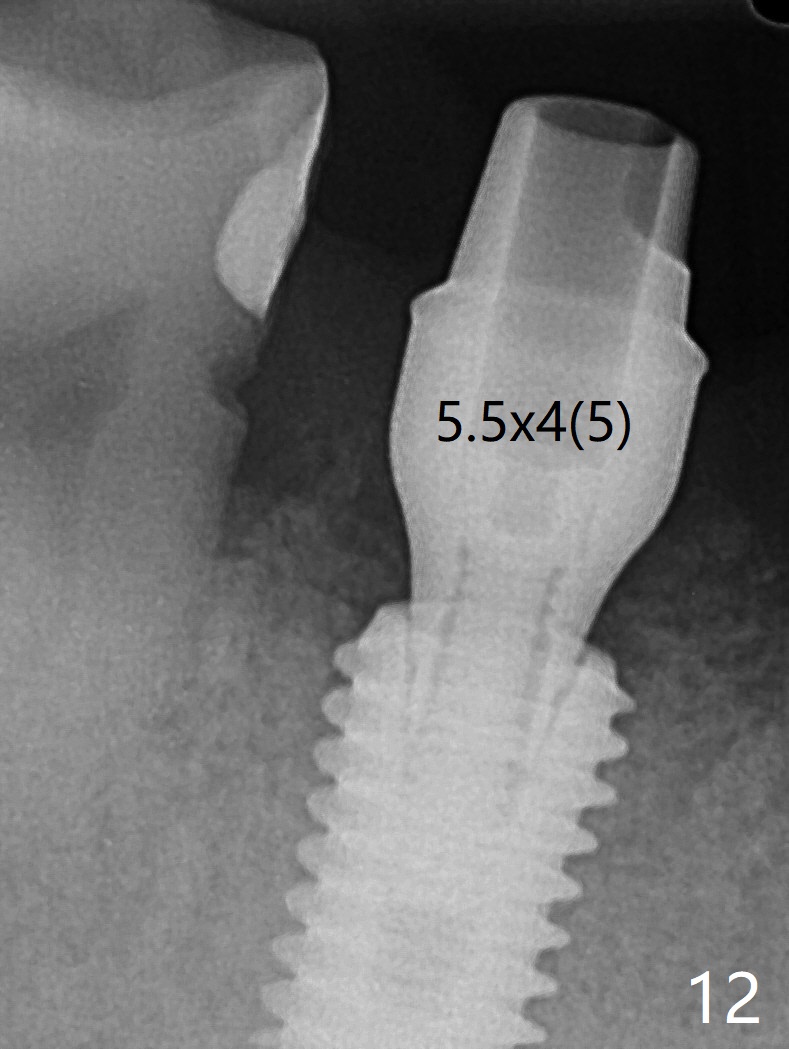

Although the tooth #30 has distobuccal root exposure (Fig.1 <), it is asymptomatic. In contrast the tooth #31 with the distoocclusal caries (*) is symptomatic. After use of 2 mm drill for 18 mm (lingual gingival margin), a calculated parallel pin is inserted (Fig.2 (D: 2 distal roots of the tooth #30)). It appears that a 11.5 mm long implant is appropriate for the site; a 5 mm cuff is expected. Following 4.8 mm drill, a 5.5x11.5 mm implant is placed initially (Fig.3) with an apical space (*) and clearance from the Inferior Alveolar Canal (red dashed line). The implant is placed deeper with placement of a 6.5x4(5) mm abutment and bone graft (*, Fig.4,5). After placement of collagen membrane over the graft, an immediate provisional is fabricated (Fig.6 P) with clearance from the opposing tooth (Fig.7 *). There is no bone loss 3.5 months postop (Fig.8). In fact the abutment has not been seated completely since its placement (Fig.4,5,8). The crown/abutment dislodges 3 years 3 months post cementation (Fig.9). The latter occurs for long incubation time because of opposing partial denture (Fig.10). After trimming proximal surfaces (Fig.11: arrowheads), the abutment remains incompletely seated (Fig.11) due to possible crestal bone interference (Fig.11 *). The smaller abutment by itself remains unseated (Fgi.12). One size small one is completely seated (Fig.13). Impression is taken. Two weeks later the abutment margin is supragingival. After screw torque at 20 Ncm, the crown is cemented with access hole. Excess cement is removed.